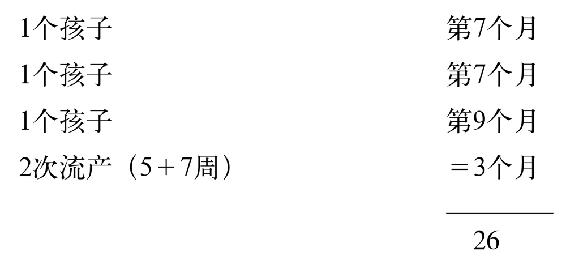

141 患者不靠我的幫助自己已經發現了夢的解釋,他聲稱自己很滿意。他的分析師卻不滿意,對他而言以上的揭示還沒有窮盡決定無意識產物的可能性。聯繫到數字5,患者詳細解釋說在3個夭折的孩子中,1個生於第9個月,2個生於第7個月。他還強調他的妻子有2次流產,1個在第5周時,1個在第7周時。如果我們把這些數字相加我們得到最終數字26: